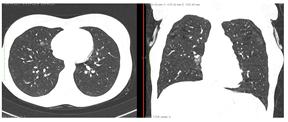

2. Наличие клинических проявлений, указанных в п. 1, в сочетании с характерными изменениями в легких по данным компьютерной томографии (КТ) (см. Приложение 1 настоящих рекомендаций) вне зависимости от результатов однократного лабораторного исследования на наличие РНК SARS-CoV-2 и эпидемиологического анамнеза.

- Изменения при КТ (рентгенографии), типичные для вирусного поражения (объем поражения минимальный или средний; КТ 1-2)

- Изменения в легких при КТ (рентгенографии), типичные для вирусного поражения (объем поражения значительный или субтотальный; КТ 3-4)

- Изменения в легких при КТ (рентгенографии), типичные для вирусного поражения критической степени (объем поражения значительный или субтотальный; КТ 4) или картина ОРДС.

КТ имеет высокую чувствительность в выявлении изменений в легких, характерных для COVID-19. Применение КТ целесообразно для первичной оценки состояния ОГК у пациентов с тяжелыми прогрессирующими формами заболевания, а также для дифференциальной диагностики выявленных изменений и оценки динамики процесса. КТ позволяет выявить характерные изменения в легких у пациентов с COVID-19 еще до появления положительных лабораторных тестов на инфекцию с помощью МАНК. В то же время, КТ выявляет изменения легких у значительного числа пациентов с бессимптомной и легкой формами заболевания, которым не требуется госпитализация. Результаты КТ в этих случаях не влияют на тактику лечения и прогноз заболевания при наличии лабораторного подтверждения COVID-19. Поэтому массовое применение КТ для скрининга асимптомных и легких форм болезни не рекомендуется.